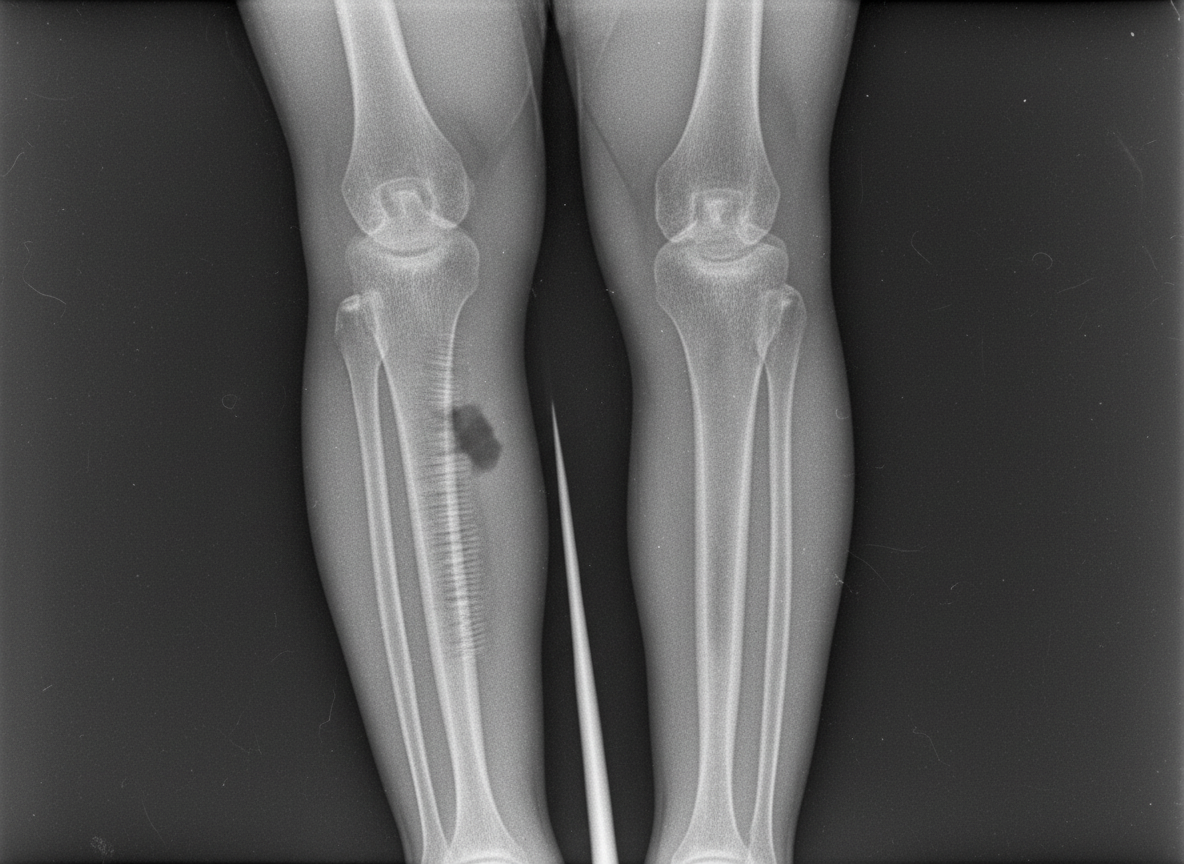

Question 8: A 10-year-old boy presents with the physical findings shown in the image, characterized by inward angulation of the elbows. What is the most likely diagnosis?

- A. Cubitus varus deformity (Correct Answer)

Explanation: ***Cubitus varus deformity*** - The image clearly illustrates an **inward angulation of the elbow** (gunstock deformity), which is characteristic of **cubitus varus**. This often occurs after a supracondylar fracture of the humerus that heals with malunion. - This deformity typically results in a decreased or reversed carrying angle of the elbow. *Madelung deformity* - This is a rare congenital anomaly characterized by **dorsal and radial bowing of the distal radius** and premature fusion of the ulnar physis. - It primarily affects the wrist, leading to a visible prominence of the distal ulna and carpal bone subluxation, which is not depicted in the elbow region in the image. *Nursemaid's elbow* - This is a common injury in young children where the **radial head is subluxated** from the annular ligament, often due to a sudden pull on the forearm. - It presents as acute pain and refusal to use the arm, but does not involve a chronic structural deformity or angulation of the elbow joint as shown in the image. *Klippel-Feil syndrome* - This is a rare congenital disorder characterized by the **fusion of two or more cervical vertebrae**. - Its primary manifestations are a short neck, low posterior hairline, and restricted neck movement, with no direct involvement or deformity of the elbow joint itself.